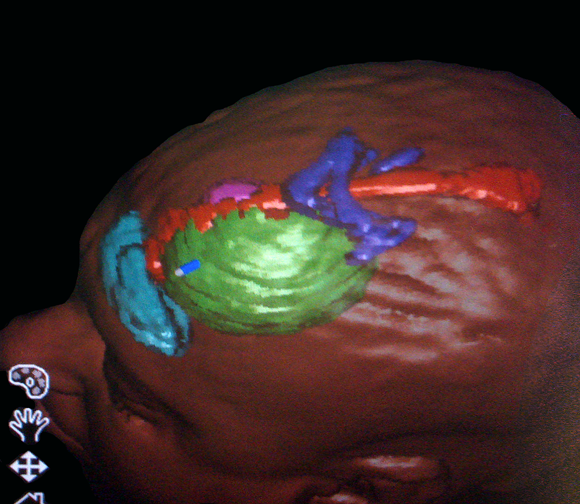

Ενδείξεις Η κύρια χρήση της νευροπλοήγησης είναι στη χειρουργική των χωροκατακτητικών εξεργασιών του εγκεφάλου, όπως οι όγκοι και τα ενδοεγκεφαλικά αποστήματα. Μπορεί επίσης να χρησιμοποιηθεί για την λήψη βιοψιών με στερεοτακτική μέθοδο, χωρίς όμως να χρειάζεται να τοποθετηθεί στερεοτακτικό πλαίσιο στην κεφαλή του ασθενούς. Περιγραφή Η μέθοδος συνίσταται στην δημιουργία μιας τρισδιάστατης ανασύνθεσης με ψηφιακό τρόπο ενός μοντέλου του εγκεφάλου του ασθενούς (με βάση τις πληροφορίες που λαμβάνονται από μια μαγνητική, ή σπάνια αξονική, τομογραφία του εγκεφάλου που πραγματοποιείται με ειδικό πρωτόκολλο), και στην χρήση αυτού του μοντέλου στο χειρουργείο για την ακριβή εύρεση της θέσης της χωροκατακτητικής εξεργασίας. Η ανασύνθεση των εικόνων γίνεται με την βοήθεια υπολογιστή και ειδικού εξοπλισμού και το ίδιο ισχύει για την ταύτιση του μοντέλου με την πραγματική θέση της κεφαλής στο χειρουργείο. |

Νευροπλοήγηση σε ασθενή με κροταφικό όγκο εγκεφάλου. Ο όγκος με πράσινο περίγραμμα, η άνω κροταφική έλικα που πρέπει να διατηρηθεί με ρόζ περίγραμμα. |

Στο μοντέλο αυτό μπορούν να συνεισαχθούν και πληροφορίες από άλλες ακολουθίες της μαγνητικής τομογραφίας, π.χ. λειτουργικές ακολουθίες όπου απεικονίζονται θέσεις κέντρων του λόγου ή της κίνησης ή ακολουθίες δεσμιδογραφίας όπου απεικονίζονται νευρικές οδοί στο βάθος του εγκεφάλου. Ο χειρουργός έχει έτσι την δυνατότητα να σχεδιάσει προεγχειρητικά την επέμβαση, αποφεύγοντας για παράδειγμα προσπελάσεις που αυξάνουν τον κίνδυνο τραυματισμού ευγενών περιοχών του εγκεφάλου ή μεγάλων αγγείων. Η ταύτιση του ψηφιακού μοντέλου με τον προεγχειρητικό σχεδιασμό και της πραγματικής ανατομίας γίνεται στο χειρουργείο με την |